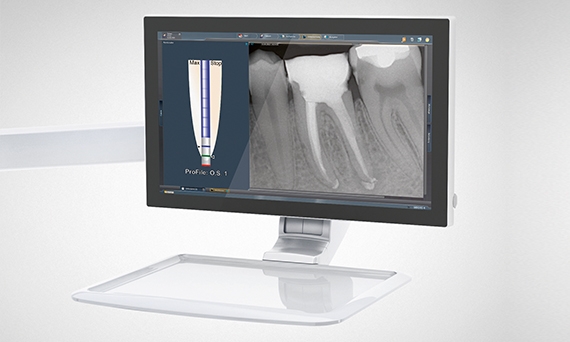

为了让您完全专注于治疗的中心——患者口腔,我们致力于提供让您更容易保持专注的功能。用于种植和根管治疗的牙科治疗装置插件正是为此目的而设计的。通过 Sivision 监视器上的显示,您可以在视野中获得相关参数。

在用户界面上显示 ApexLocator 及其声信号旁边,它也可以显示在 Sivision 监视器上。牙科治疗设备插件可以直接在监视器上查看根管末端距离。在 ApexLocator 旁边,还会显示所选文件。